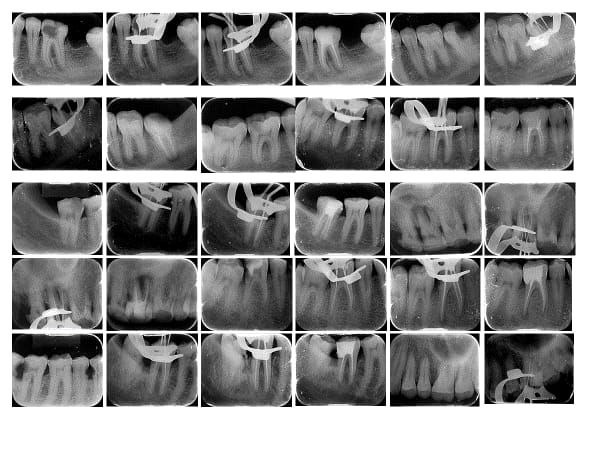

BDS ,MDS (Conservative Dentistry and Endodontics)

Dr. Ananya graduated from the prestigious Manipal College of Dental Sciences, Manipal with a BDS degree and completed her postgraduation (MDS) in Conservative Dentistry and Endodontics from IDS, Bareilly. She has been passionately practicing dentistry since then. With the desire to pursue both academics and also run a clinical practice she continues to serve as a teaching faculty at a dental college in Lucknow and manages her clinic in the evening. Her meticulous approach, experience and desire to provide the best treatment has always enabled her to save teeth in a relatively painless manner. She is also a member of